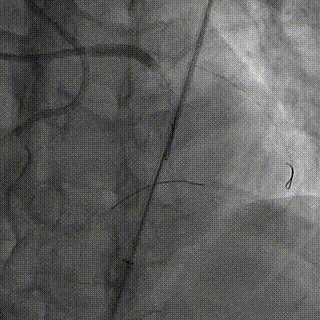

PCI过程

双侧造影,RCA 7F AL1.0,Runthrough导丝置于远端。

LCA 7F XB3.5,Cosair135,尝试Pilot200失败,进入假腔,Judo3成功通过闭塞段,换入Pilot150后,仍然进入假腔,再次使用Judo导丝,进入前降支远端,微导管造影,证实为真腔内,送入工作导丝。

Tip injection确认真腔,更换runthrough,2.0*20mm球囊预扩。

IVUS提示LAD近中段弥漫钙化,接近270度,钙化长度约26mm

LAD Stent 2.5*36mm,3.0*29mm ;Immediate image ,TIMI3

继续开通LCX,Pilot200 成功通过闭塞段,Tip injection 确认真腔

更换runthrough,Ballon dilatation 2.0*20mm,2.75*15mm

LCX Stent 2.5*36mm, Immediate image ,TIMI3

IVUS LCX-LM,RUN2

支架膨胀、贴壁良好,LCX开口MSA 5.68mm²,LM MLA 5.67mm²。

NC 3.0*15mm,3.5*15mm后扩张;LM stent 4.0*19mm

Runthrough 掏LCX支架网眼,退LAD导丝,送入 NC 3.5*15mm扩张,优化开口支架形态

IVUS LAD-LM,RUN3,LAD口部MSA 9.03mm²,LM MSA 10.18mm²

NC Ballon dilatation 3.0*15mm,3.5*15mm,4.0*12mm

Final result